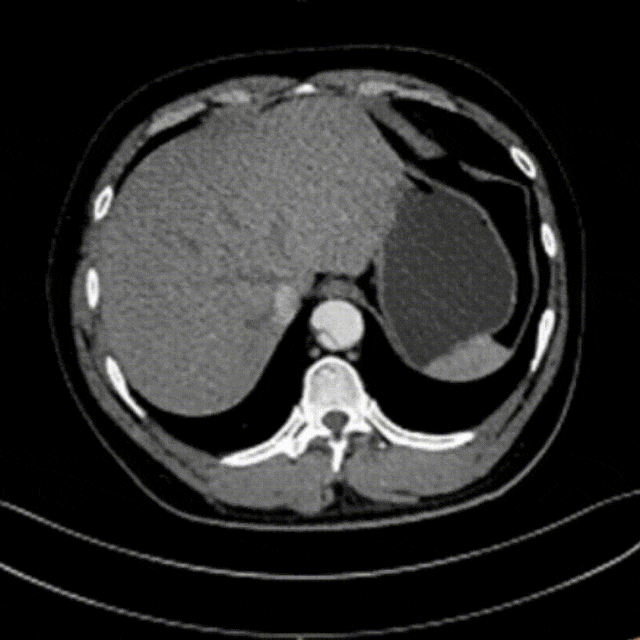

48岁男性,胸腹痛20小时,右下肢一过性麻木,TEVAR治疗

影像学表现:主动脉破裂或先兆破裂、胸腔积血、假腔快速扩张、原发破口逆向撕裂、血肿向近端蔓延、远端脏器供血障碍等。

影像学特征分析:复杂型TBAD组患者III型弓比例较高,近端破口多位于3区,远端累及区域更广,假腔直径更大。